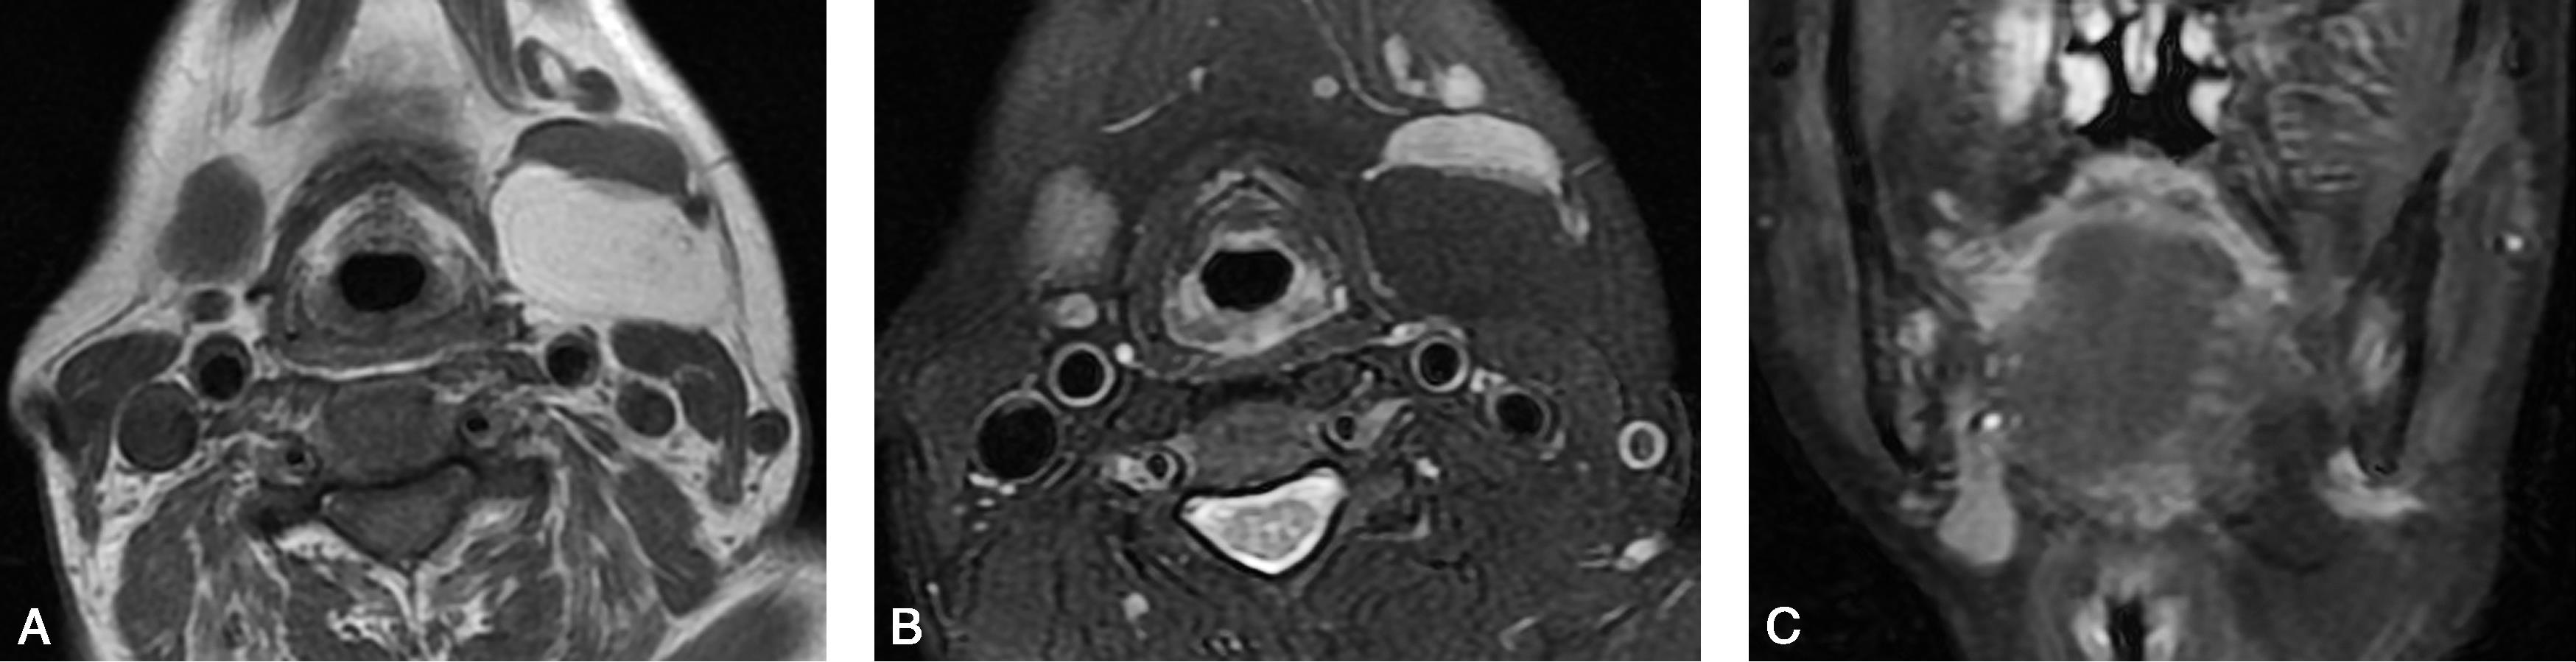

患者,女,43岁,发现左侧颌下肿物1余年(图5-5-2)。

图5-5-2 脂肪瘤2

MRI轴位T

1

WI(图A)呈均匀高信号;轴位水相脂肪抑制T

2

WI(图B)和冠状位脂肪抑制T

WI(图C)呈均匀低信号。